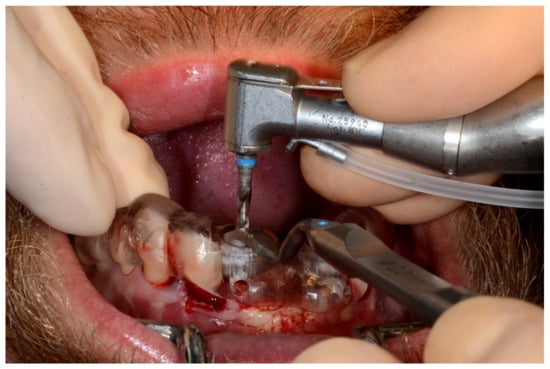

Figure 8.

Implant bed preparation by using guided drills inserted into specific ad hoc drill handles.